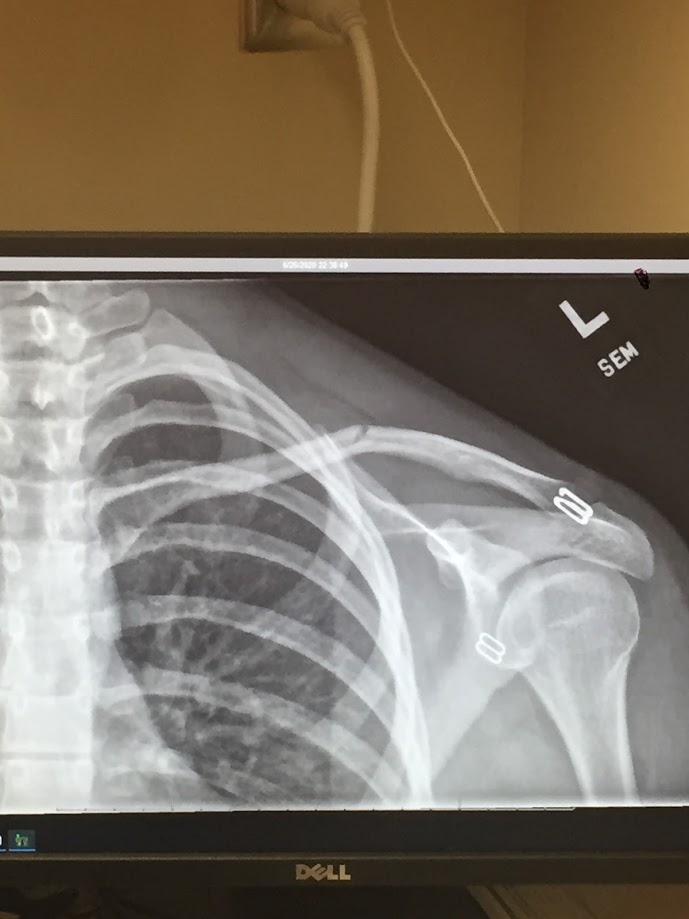

I was all set to write my blog yesterday when I got a call from Lilli at 9:40… “Mom, I’m at Madrona Park and I broke my collar bone.” John and I got into the truck and drove down to the park. It was clear that she had, indeed, broken her collar bone when she fell off her long-board. It was not looking like, or in the spot it should have been. We loaded her up and headed to the ER. She was eerily calm and nauseated. We had to make a stop at home for an insurance card. For some reason, my card was not in my wallet… neither was Lilli’s card. When we got to the ER only one parent was allowed in the back with her. She wanted me to be with her. John sat in the car. The doctor was funny. So was the nurse. She was taken to e-ray rather quickly. When she got back from x-ray, the doctor let me see the results. He said it was a green stick. It didn’t look very “green stick” to me. It was open fairly far on the top but the bottom of the clavicle was still in tact. They put her in a sling, wrote an order to see an orthopedic doctor, and set us home. It was not well after 11, but she wanted Taco Bell so we stopped for a taco. However, on the way home, I noticed the truck was running funny and suddenly got very hot. I pulled over to the side of the road just as the check gauges sign came on. John called the tow truck. It was now after midnight. He also called Kimber and Ray to see if they could help get at least, Lilli and me home. The tow truck never came. Ray took a little while to get there. We were finally home and settled around 2 am. She had to sleep in the recliner because it hurts to lay down. She wanted me to sleep by her, in case she needed help during the night. I slept on the couch. She got up a couple times and I got up to help her. Then, the power went off at around 6 am. I couldn’t breath because my C-PAP stopped. Let’s just say, I am pretty tired. But I do have much to be grateful for.

Today I am grateful that Lilli will heal and we have the ability to let her lay low for the rest of the summer while her bone recovers from this trauma. I am also grateful for insurance and for a doctor that was easy to talk to… and I’m grateful he let me sneak a picture of her x-ray.